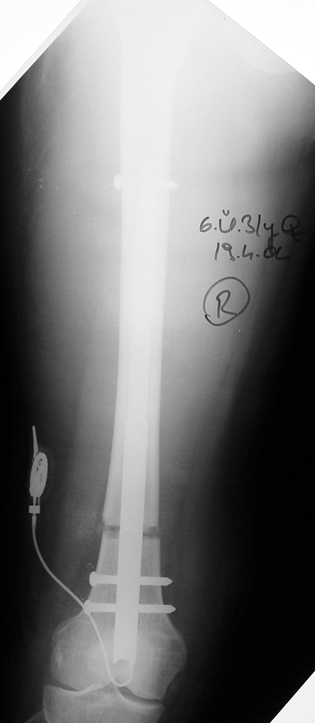

Case 2